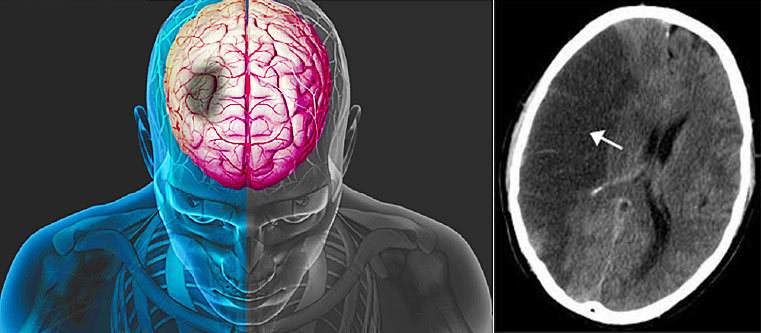

Bình thường, hệ thống dẫn truyền điện học của tim phát ra các xung điện đến từng tế bào cơ tim, qua đó khiến quả tim co bóp một cách nhịp nhàng. Rung nhĩ xuất hiện do sự rối loạn hình thành các xung động điện học của tim. Khi xuất hiện rung nhĩ: tâm nhĩ rung lên với tần số trên 350 chu kì/ phút thay vì co bóp một cách nhịp nhàng. Điều này làm hạn chế lưu chuyển của dòng máu và khiến cho máu bị quẩn lại trong nhĩ qua đó hình thành các cục máu đông và nếu cục máu đông rời khỏi nhĩ trái gây tắc mạch não có thể gây ra đột quỵ.

Hình ảnh tắc động mạch não giữa gây nhồi máu não ở bệnh nhân rung nhĩ |

Thống kê cho thấy bệnh nhân mắc rung nhĩ có nguy cơ bị đột quỵ cao gấp 5 lần người bình thường. Rung nhĩ là nguyên nhân trực tiếp gây ra khoảng 120,000 trường hợp nhồi máu não mỗi năm và chiếm 25% tổng số trường hợp đột quỵ não. Đột quỵ não ảnh hưởng nghiêm trọng đến chất lượng cuộc sống của các bệnh nhân, chính vì vậy việc phòng ngừa tai biến đột quỵ là mục tiêu nền tảng trong điều trị rung nhĩ. Mặc dù có nhiều phương pháp để phòng ngừa đột quỵ, tuy nhiên việc sử dụng các chống đông luôn là phương pháp đầu tay trong điều trị rung nhĩ. Các thuốc chống đông thực sự hiệu quả trong việc làm giảm nguy cơ nhồi máu não.